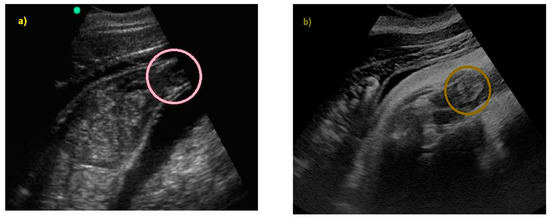

Pregnancy and Fetal Development: Cephalic Presentation and Other Descriptive Ultrasonographic Findings from Clinically Healthy Bottlenose Dolphins (Tursiops truncatus) under Human Care

3. Results